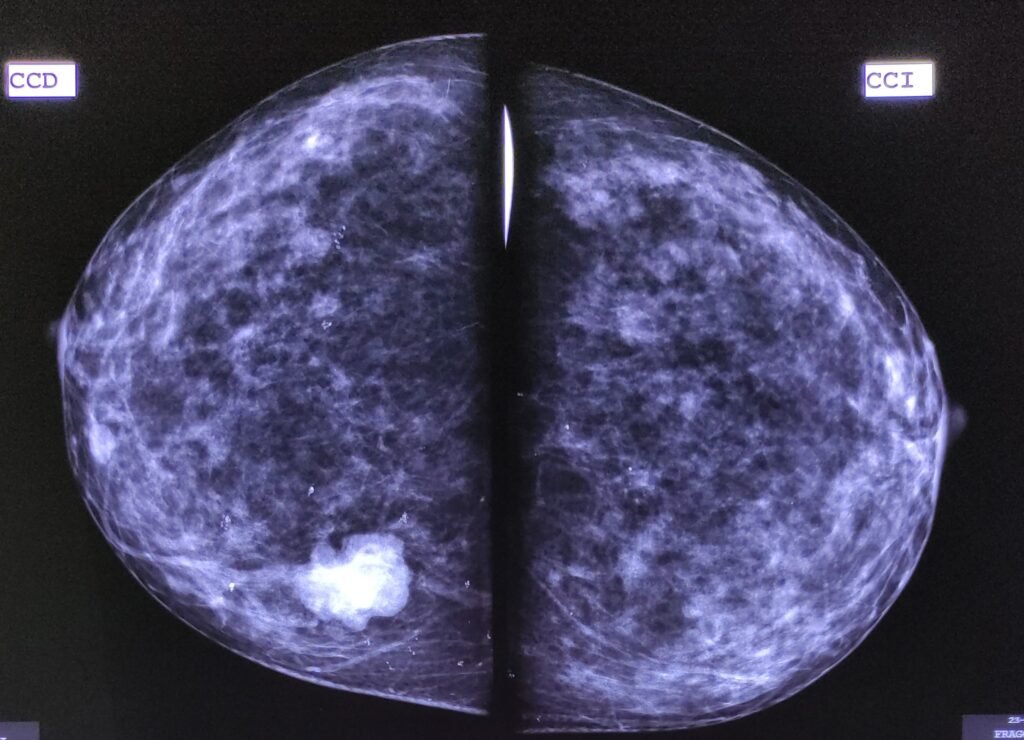

Una mastografía puede reportar:

- Calcificaciones

- Asimetrías

- Nódulos

- Distorsiones del tejido

El sistema BI-RADS ayuda a clasificar estos hallazgos y orientar los siguientes pasos.